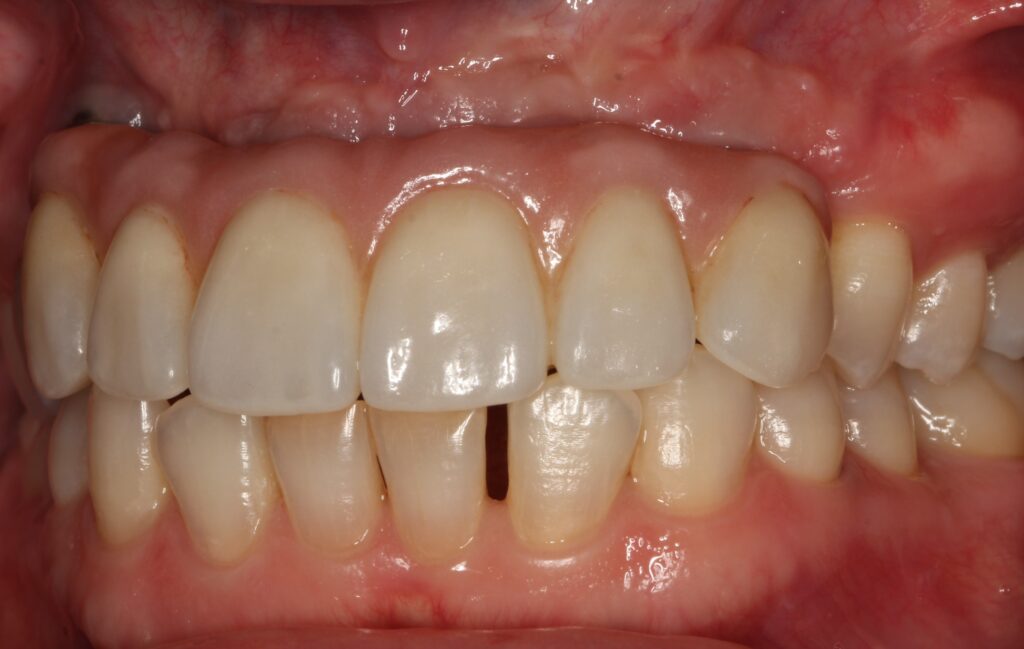

A selection of partial arch fixed implant bridge patients